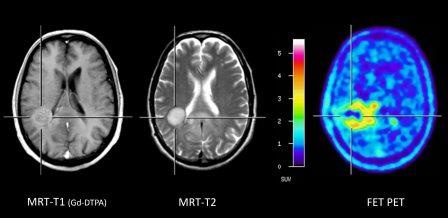

Differenzierung zwischen strahlenbedingten Veränderungen und Rezidivtumor

Ein weiteres Problem für die MRT-Diagnostik stellt die Unterscheidung eines Tumorrezidivs von unspezifischen posttherapeutischen Veränderungen dar. Eine posttherapeutisch auftretende pathologische Kontrastmittelaufnahme in der Tumorregion erlaubt keine Unterscheidung zwischen einem Tumorrezidiv und unspezifischen Veränderungen. In dieser Situation kann die FET PET mit einer Sensitivität und Spezifität von ca. 90 % ein Tumorrezidiv von einer Radionekrose differenzieren. Auch zur Unterscheidung einer Rezidivmetastase von einer strahlenbedingten Veränderung nach vorheriger Bestrahlung von Hirnmetastasen (z. B. einzeitige Radiochirurgie) hat sich die FET PET bewährt.